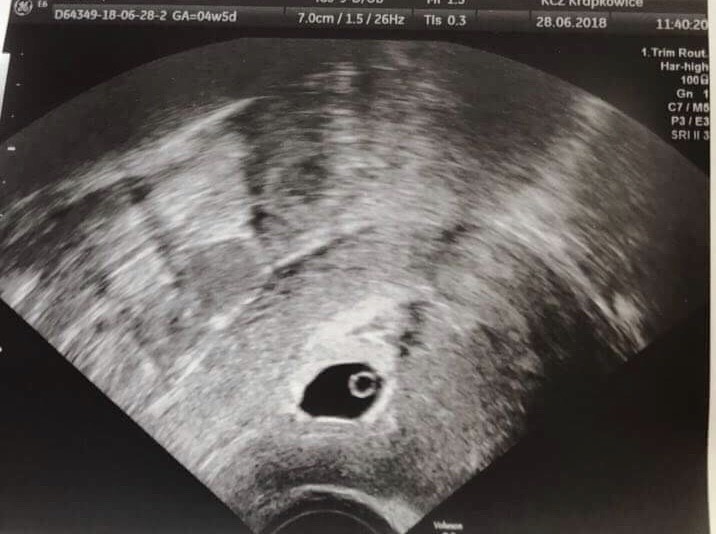

U mnie w 26 dniu cyklu był taki test Zobacz załącznik 967433 i taka beta Zobacz załącznik 967434 a za 3 dni takie usg Zobacz załącznik 967435